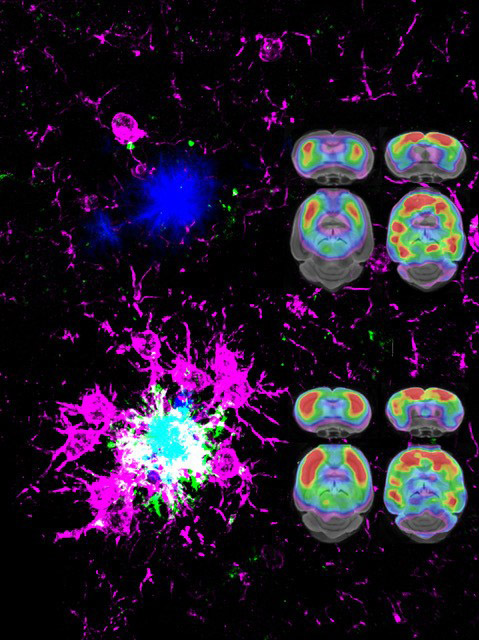

Coding variants in the triggering receptor expressed on myeloid cells 2 (TREM2) are associated with late-onset Alzheimer’s disease (AD). We demonstrate that amyloid plaque seeding is increased in the absence of functional Trem2. Increased seeding is accompanied by decreased microglial clustering around newly seeded plaques and reduced plaque-associated apolipoprotein E (ApoE). Reduced ApoE deposition in plaques is also observed in brains of AD patients carrying TREM2 coding variants. Proteomic analyses and microglia depletion experiments revealed microglia as one origin of plaque-associated ApoE. Longitudinal amyloid small animal positron emission tomography demonstrates accelerated amyloidogenesis in Trem2 loss of-function mutants at early stages, which progressed at a lower rate with aging. These findings suggest that in the absence of functional Trem2, early amyloidogenesis is accelerated due to reduced phagocytic clearance of amyloid seeds despite reduced plaque-associated ApoE.